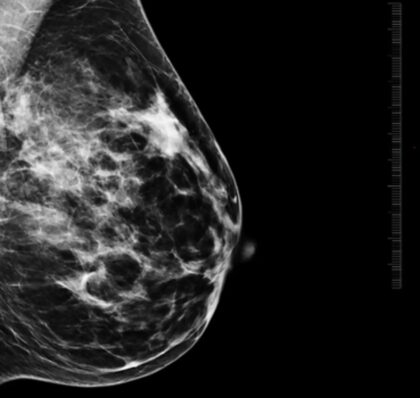

Lekári pri hodnotení mikrokalcifikátov sledujú viacero znakov, napríklad ich veľkosť, tvar, hustotu, rozloženie v prsníku či to, ako sa menia v čase. Práve tieto informácie pomáhajú určiť, či ide o bežný a neškodný nález, alebo o zmenu, ktorú treba podrobnejšie vyšetriť.

„Mikrokalcifikáty môžu byť v úplne skorom štádiu viditeľné len na mamografii, často ide o zmeny veľké len niekoľko milimetrov. Práve preto je mamografické vyšetrenie také dôležité a nenahraditeľné. Väčšie zmeny môžu byť neskôr viditeľné aj na ultrazvuku,“

vysvetľuje MUDr. Alexandra Bieliková, lekárka rádiológie AGEL Mammacentra sv. Agáty.